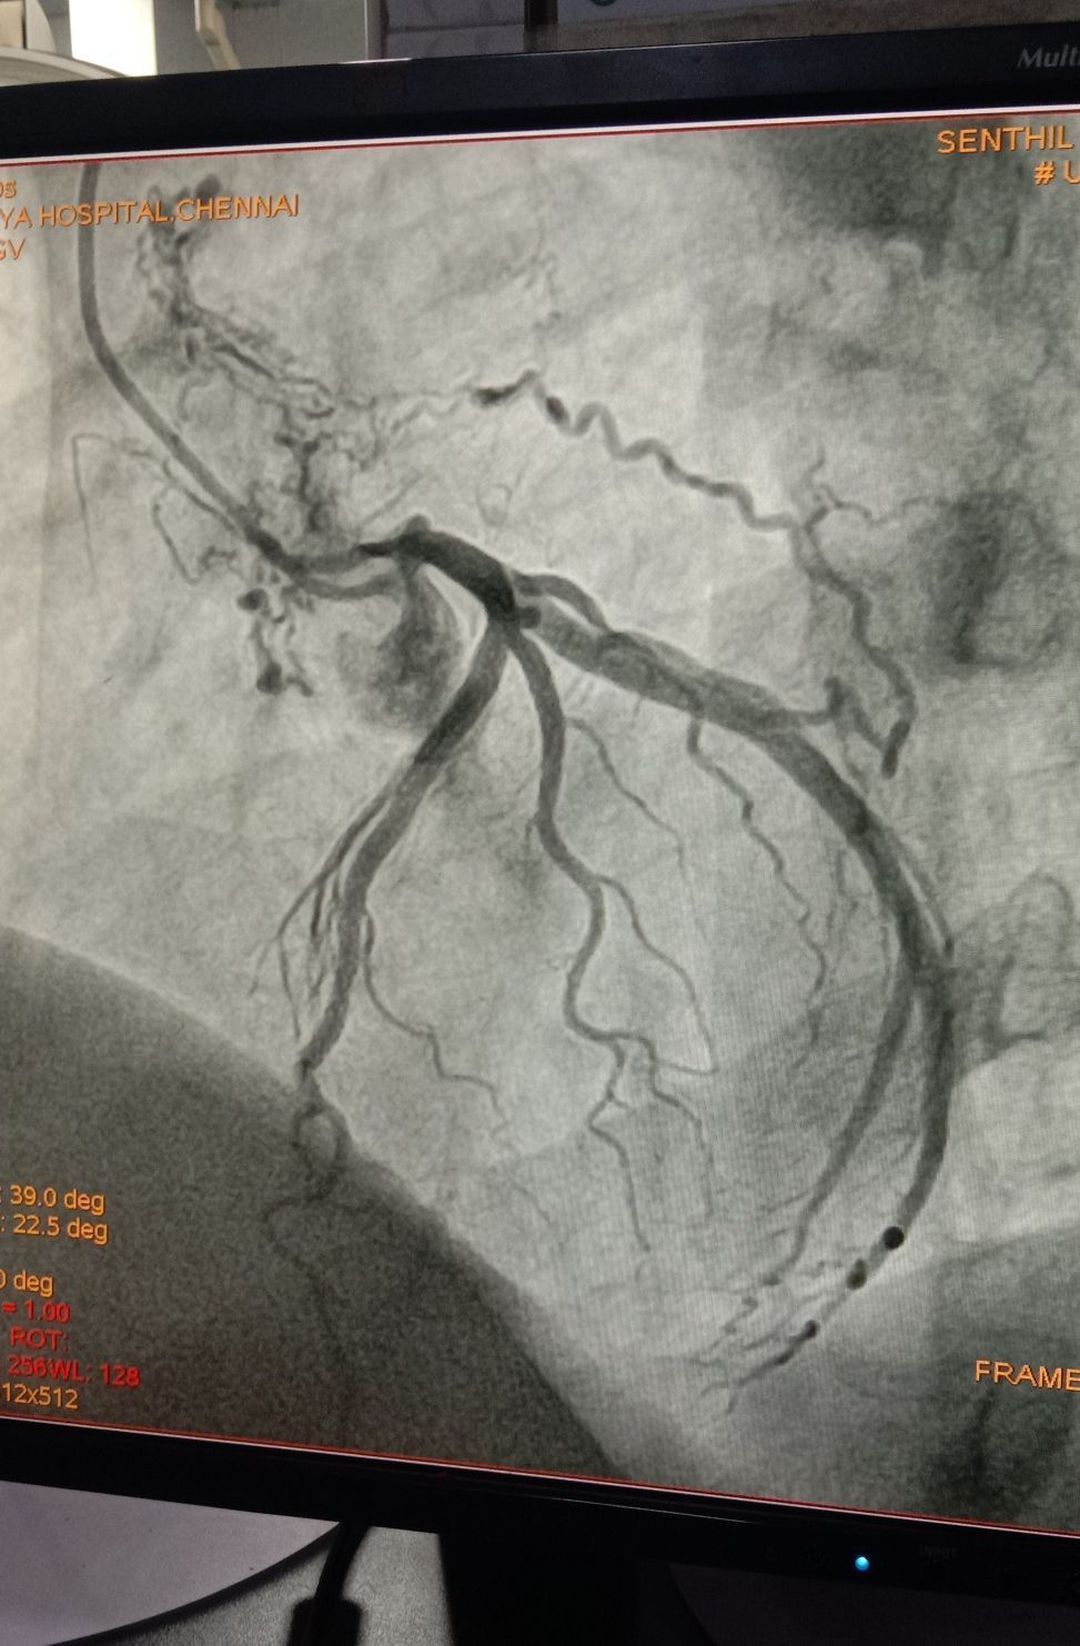

Diagnose plzz

Heart

Coronary Artery